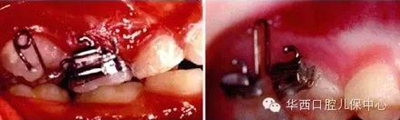

使用局部固定矯治器直立后牙